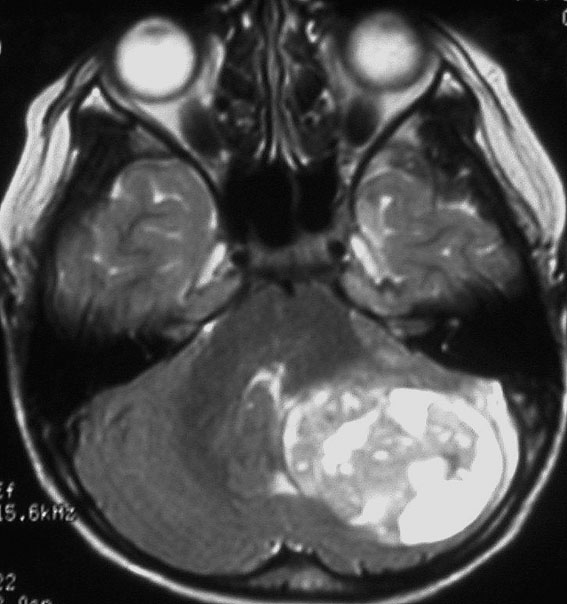

- MRIで診断します

- 境界がはっきりした腫瘍です,くりんとしています

- ガドリニウム造影剤で白く映ります(増強される)

- でも,ガドリニウム造影剤が入らなくて白く映らないものもあります

- 周囲の小脳が腫れることが多いです(脳浮腫)

- CTでは石灰化がみられることがあります

- CTでは小脳より白っぽい灰色(高密度)に写ります

この例は,小脳半球にできたものです。のう胞(水たまり)を形成しています。髄芽腫の大きな特徴は,造影剤を入れないCT(左側)で腫瘍が少し白く見えることです(灰白質より高密度といいます)。細胞密度が高いので高密度になります。この例はclassic medulloblastomaですが,MIB-1は45%に達するもので,急激な腫瘍発育を示します。